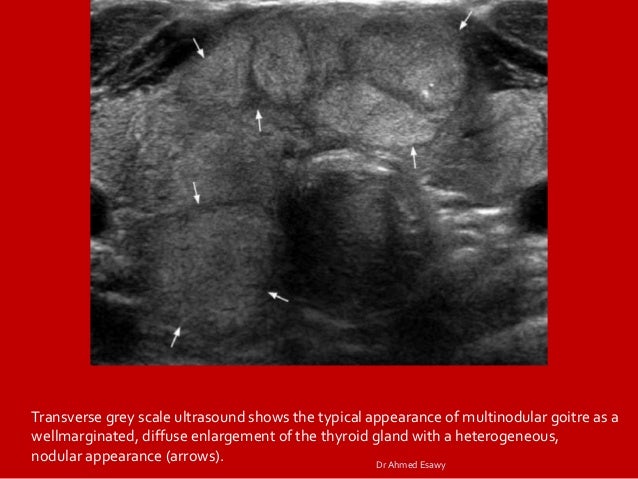

Presentation1 Pptx Radiological Imaging Of The Thyroid Gland Disease

Thyriod Gland Imaging Part 2 Full Story Diffuse Thyriod Disease Dr